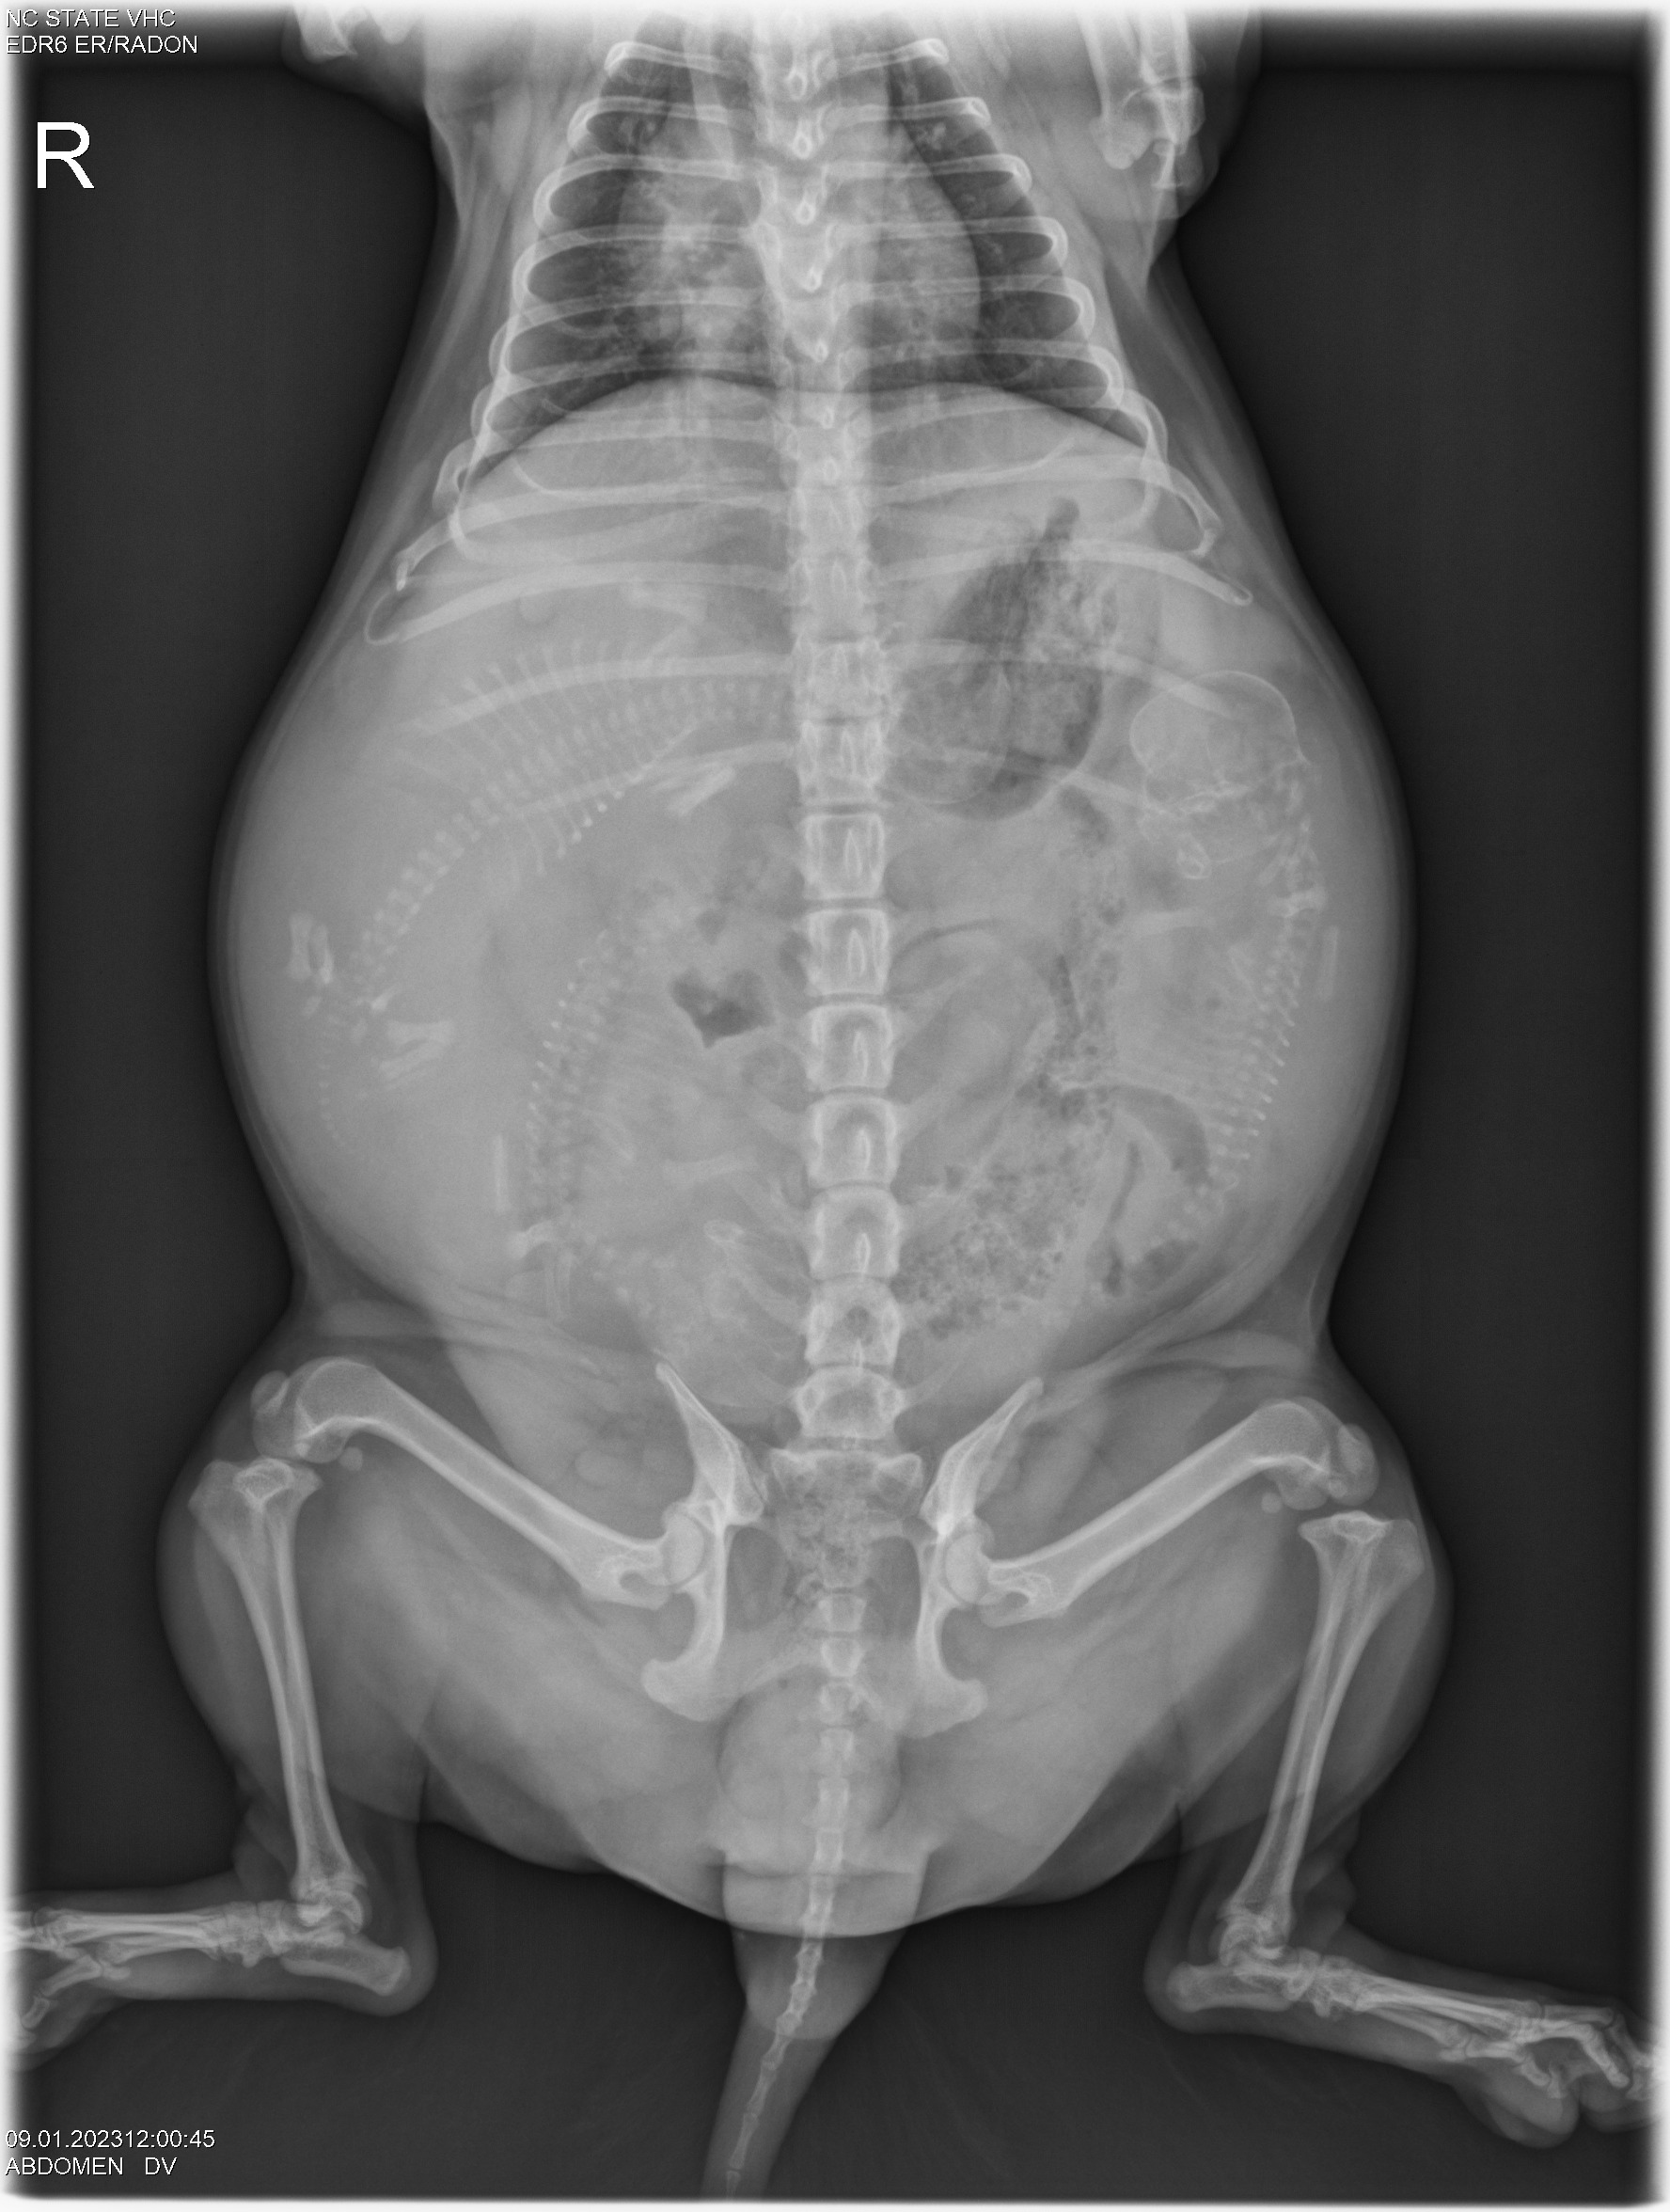

Today was x-ray day! I took both Gwynie and Siri to NC State University for abdominal x-rays. Here they are: (If you look closely, you can see the spines and perhaps the skulls of the puppies.)

Looking at the x-rays, my repro vets told me that Gwynie is carrying three puppies, and Siri is carrying two. Comparing the size of the pelvic opening of each girl with the size of the puppy skulls they are carrying, I was told for both Gwynie and Siri that the sizes are close. I was advised to have a cesarean section (c-section) for both girls. So that is what we will do.

Since Gwynie's due date is this weekend, the vets started "staging" Gwynie for a c-section. The vets checked out Gwynie's puppies using ultrasound and all looks good - good heartbeats and good GI motility. They took some blood from Gwynie and did a progesterone test. Towards the end of pregnancy, progesterone falls. Using the ultrasound results and progesterone number lets the vets decide when to do a c-section. Gwynie and I will now come back to NC State (a two-hour ride one-way) each morning for progesterone testing and ultrasound until the vets say "today is the day" for the c-section.